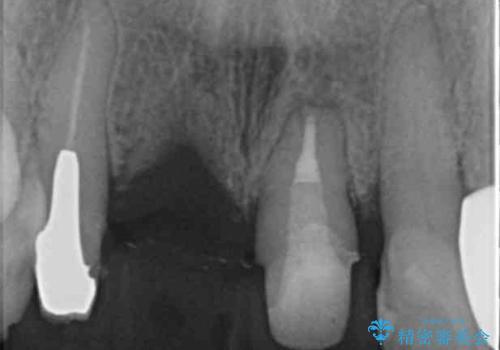

1. ぐらつく前歯 ブリッジ治療の治療前